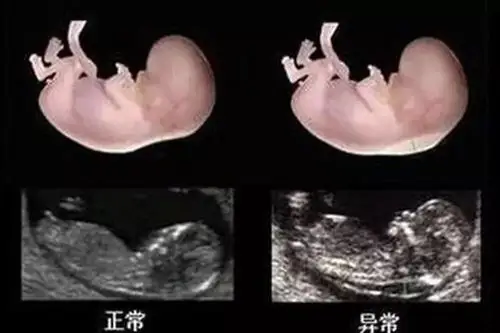

nt图有三条线是女孩怀孕12周nt图女孩的标志